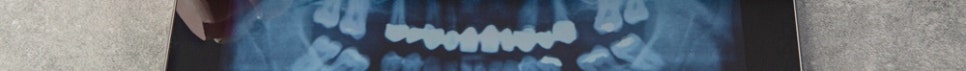

임플란트는 상실된 치아의 뿌리를 대신해 잇몸뼈에 심는 인공 치근과 그 위에 장착하는 보철물로 구성된 치료입니다. 인공 치근은 티타늄 소재의 나사 형태로, 잇몸뼈와 결합하는 과정을 거치게 됩니다. 이 결합이 충분히 이루어지면 자연치아에 가까운 저작력과 고정력을 회복하는 데 도움이 될 수 있는 것이 임플란트 치료의 기본 원리입니다.

첫째, 3D CT 촬영으로 잇몸뼈의 양과 밀도, 전반적인 구강 구조를 정밀하게 파악합니다. 둘째, Dio Navi guide와 3D 프린터를 활용한 컴퓨터 모의 수술로 임플란트를 식립할 위치와 각도를 사전에 계획합니다. 셋째, 그 계획을 토대로 임플란트를 식립하고, 당일 임시 보철물을 연결합니다. 치아 없이 지내는 기간을 줄일 수 있도록 하는 과정이기도 합니다. 넷째, 잇몸과 임플란트가 충분히 안정된 뒤 최종 보철물을 장착하는 단계로 마무리됩니다.